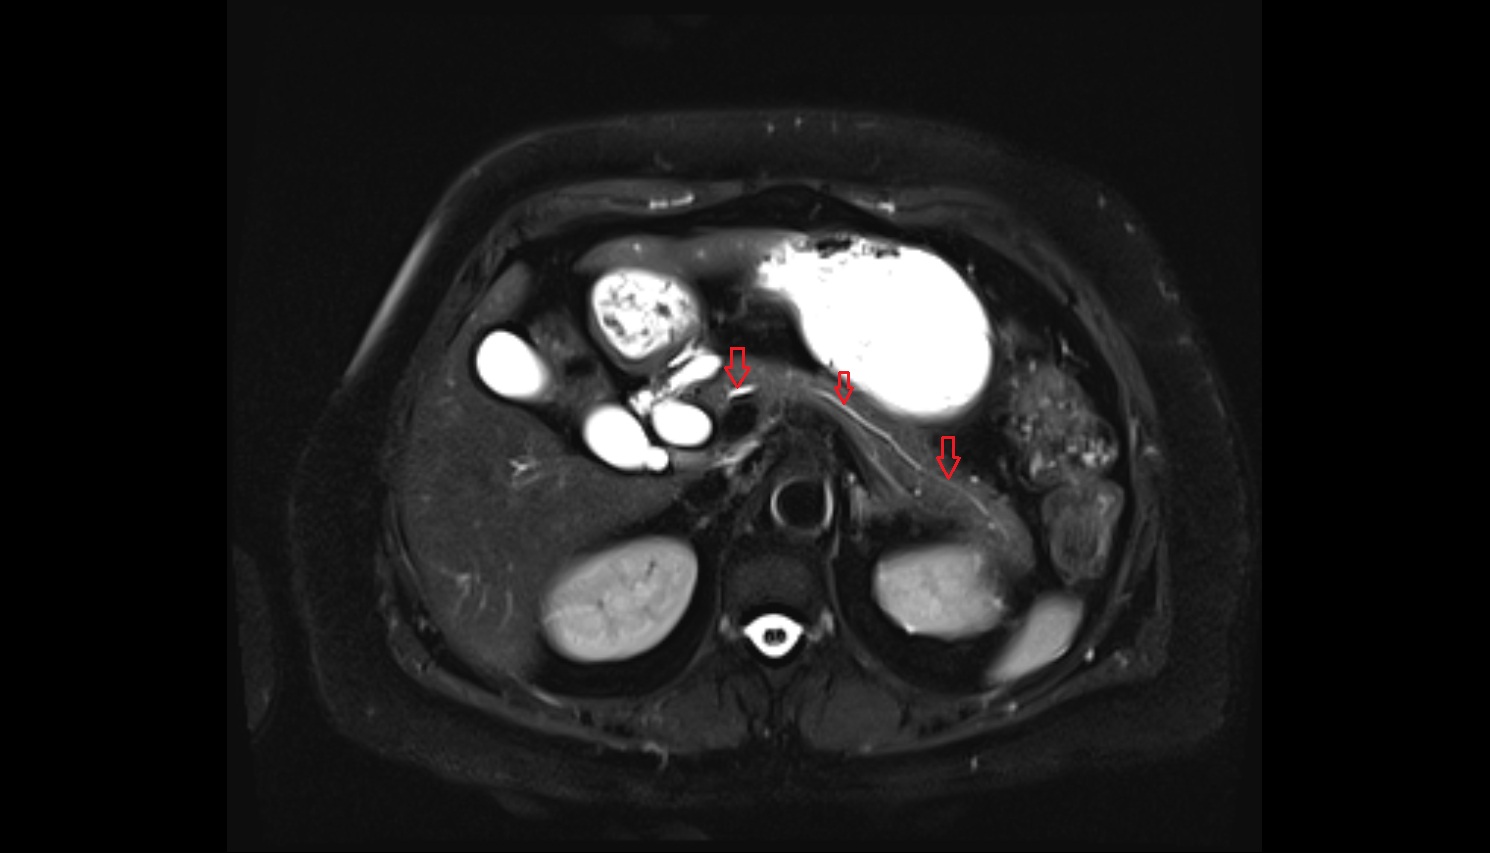

- Placenta

- Uterus (pregnancy)

- Amniotic fluid

- Umbilical cord

- Urinary Bladder in Pregnancy

- Cervix in Pregnancy

- Vagina in Pregnancy

- Fundus of uterus in pregnancy

- Fetal brain

- Fetal caudate nucleus

- Fetal thalamus

- Fetal pons

- Fetal cerebellum

- Fetal occipital lobe

- Fetal temporal lobe

- Fetal parietal lobe

- Fetal frontal lobe

- Fetal third ventricle

- Fetal fourth ventricle

- Fetal lateral ventricle

- Fetal superior sagittal sinus

- Fetal straight sinus

- Fetal transverse sinus

- Fetal sigmoid sinus

- Fetal cervical spine

- Fetal thoracic spine

- Fetal lumbar spine

- Fetal spinal cord

- Fetal Eyes

- Fetal paranasal sinuses

- Fetal tooth buds

- Maternal ovaries

- Fetal shoulder

- Fetal lungs

- Fetal Ribs

- Fetal trachea

- Fetal Heart

- Fetal aorta

- Fetal upper arm

- Fetal knee

- Fetal ankle

- Fetal foot

- Fetal thigh

- Fetal Lower Leg

- Fetal forearm

- Fetal Liver

- Fetal small bowel

- Fetal hand

- Fetal urinary bladder

- Fetal kidneys

- Fetal rectum

- Fetal elbow

- Fetal wrist

- Fetal hip

- Fetal anus

- Fetal Fingers

- Fetal buttock

- Fetal scrotum

- Fetal testis

- Fetal penis

- Fetal colon

- Fetal stomach

- Fetal spinal canal